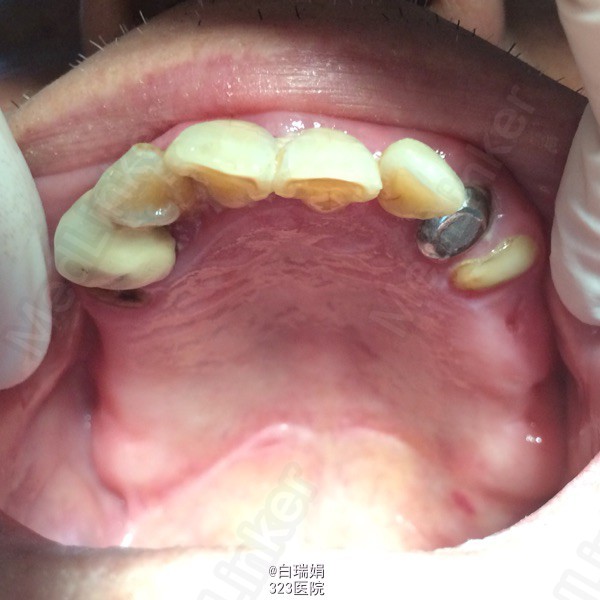

患者,男,78岁。 主诉:左上后牙疼痛不适一月余。 现病史:患者述五年前左上后牙行烤瓷冠修复,近半年来自觉松动,咬物疼痛不适,近一个月症状加重,未做处理,现前来要求检查治疗。既往体健,无全身系统疾病时,药物过敏史及传染病史。

检查:左上3至左上7烤瓷联冠,松动2度,左上3、4、5、7叩诊(➕),左上7腭侧牙根吸收至根中1/3,右上4至右上7缺失,缺牙区牙槽嵴尚可,无明显骨突骨刺;X线示左上3、4、5牙周膜间隙增宽,根尖区低密度影像,左上5远中牙槽骨吸收至根中1/3,左上7牙槽骨吸收至根尖。